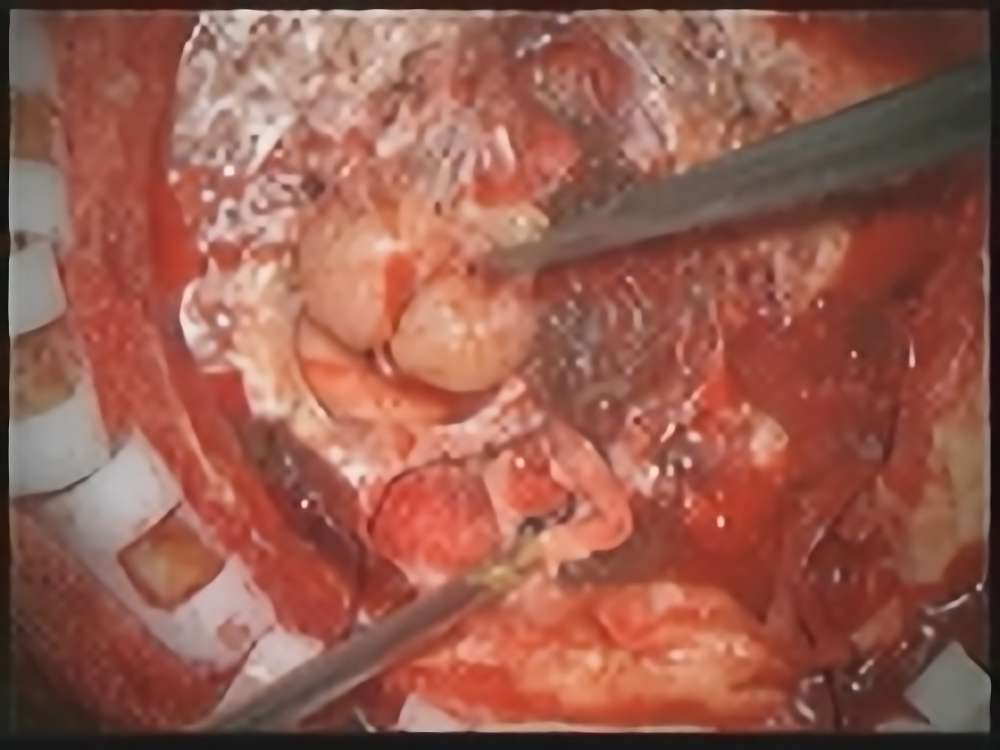

No.’21_62  摘出 中

No.’21_62 摘出 後